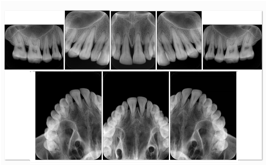

- OO-1. Intra-oral Full Mouth Series Structured Display